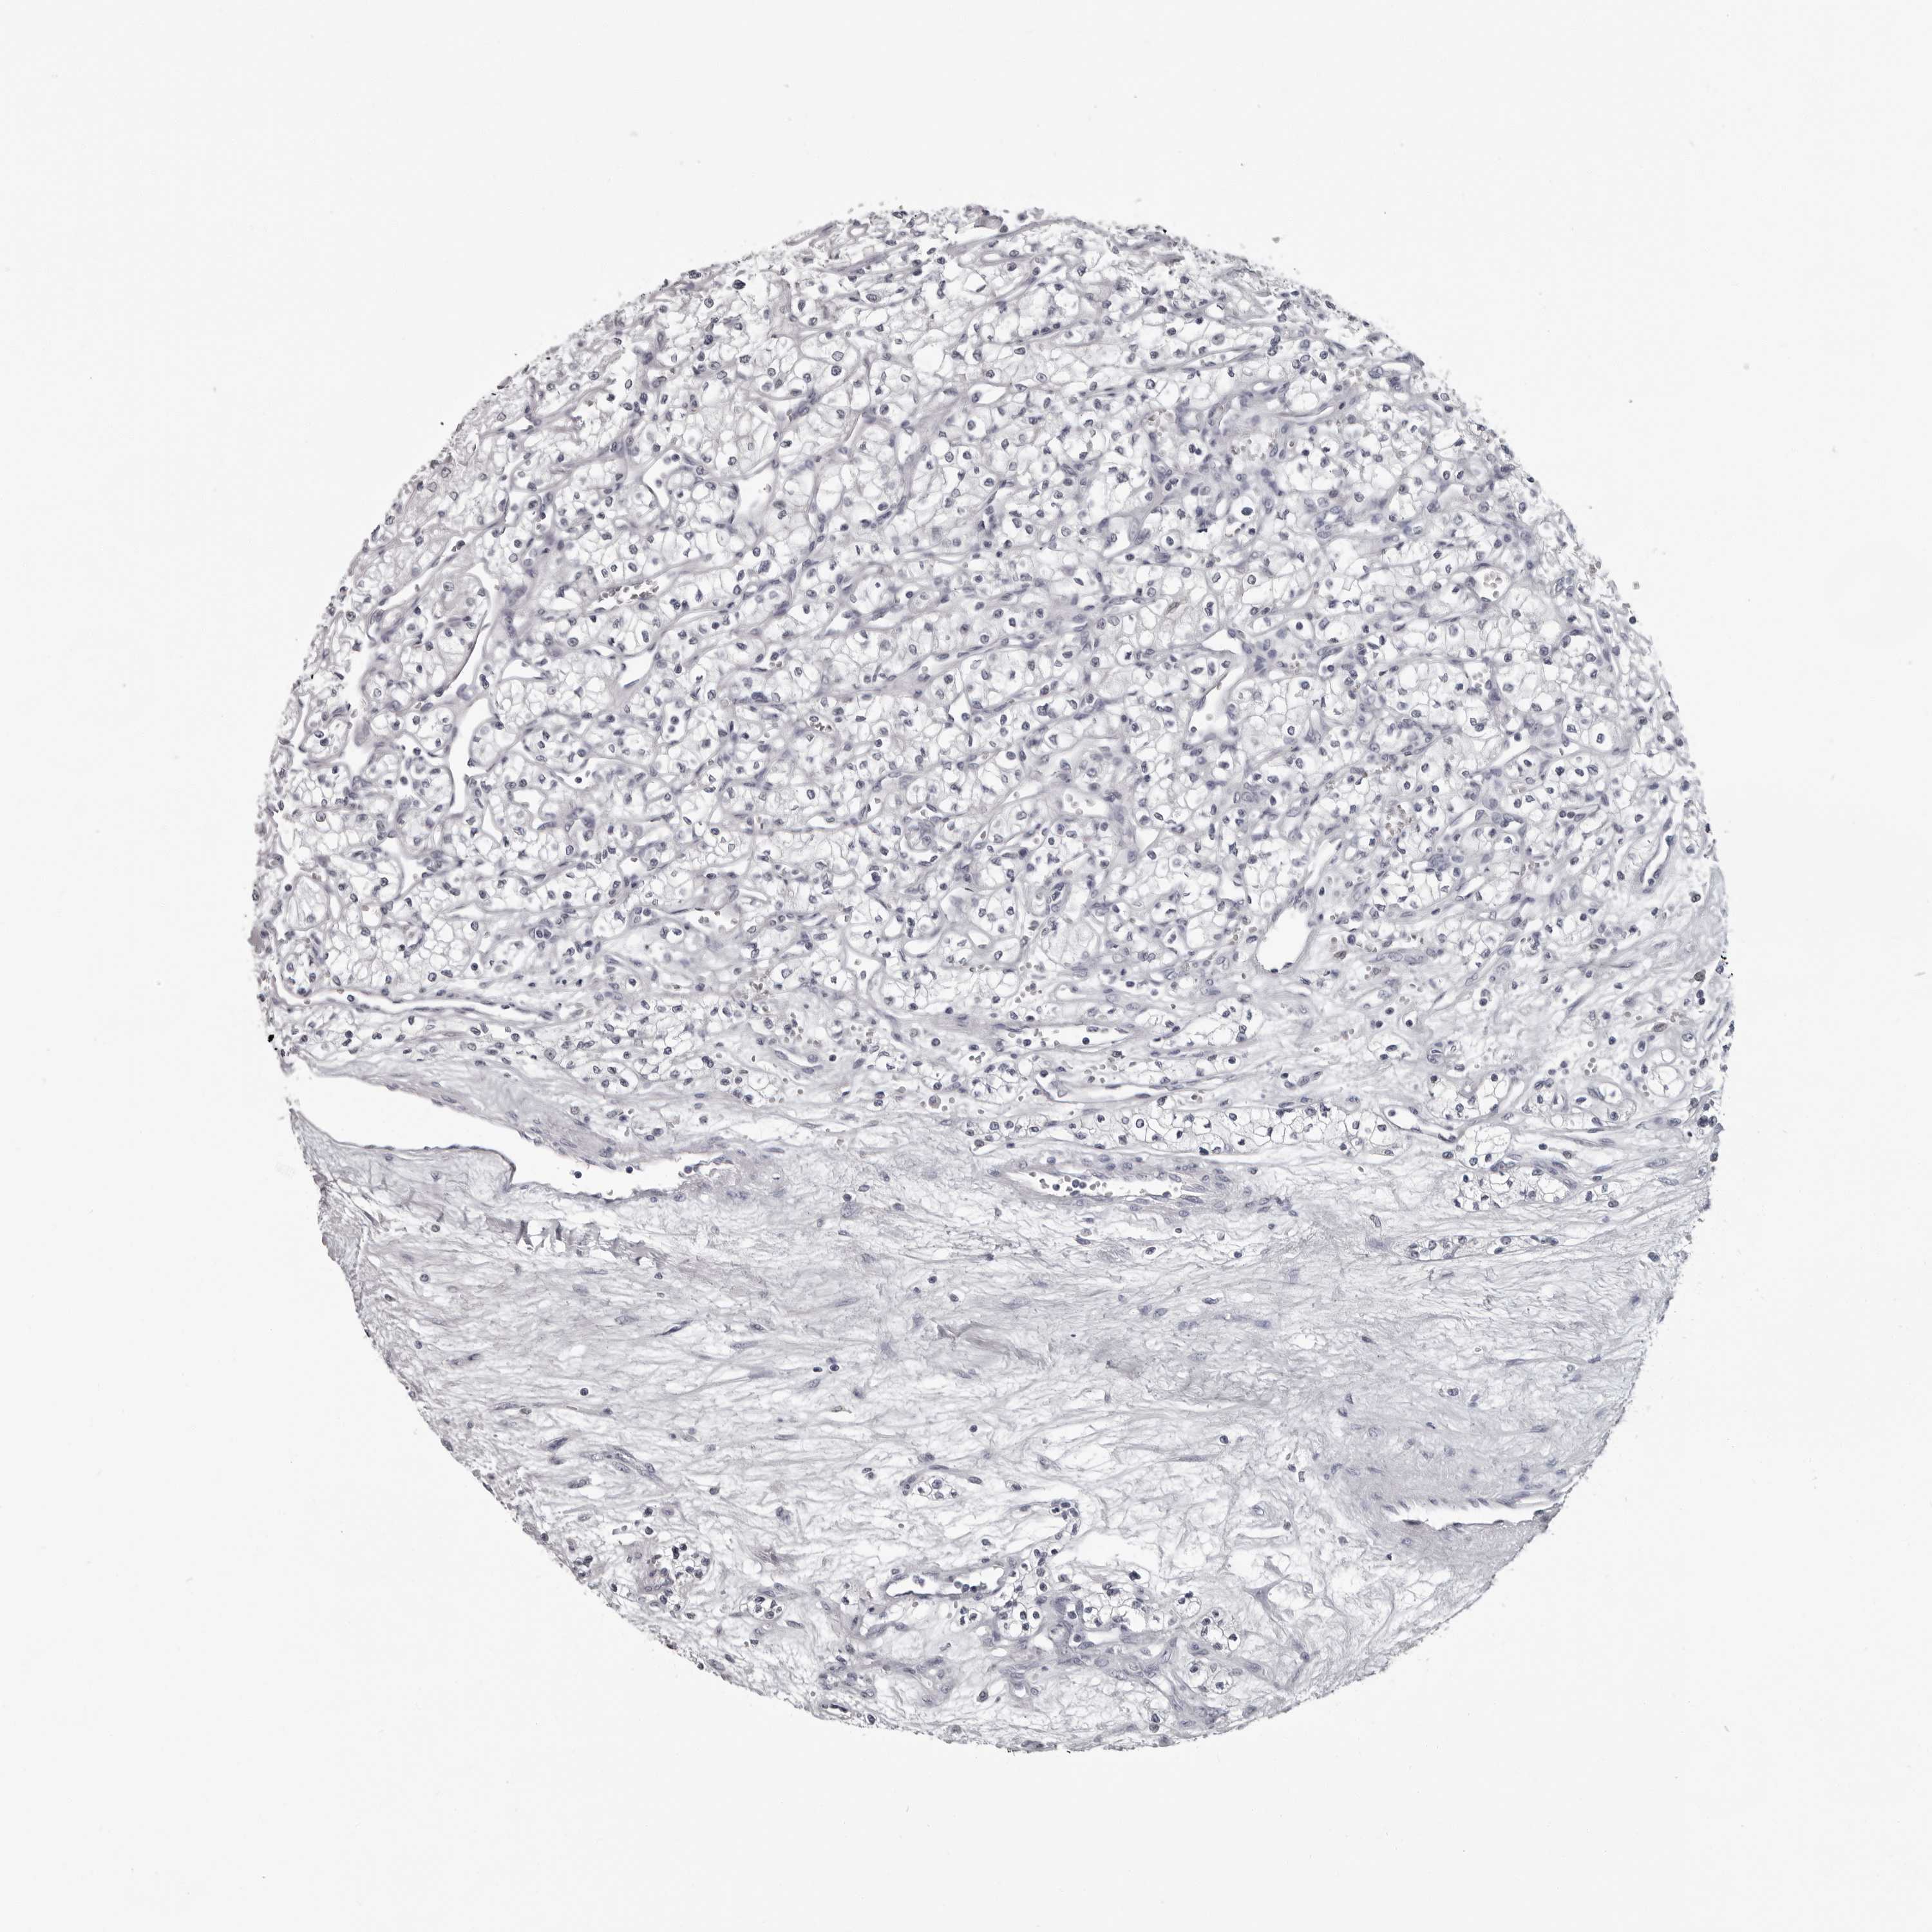

KIDNEY RENAL CLEAR CELL CARCINOMA (VALIDATION) - Interactive survival scatter ploti

The Survival Scatter plot shows the clinical status (i.e. dead or alive) for all individuals in the patient cohort, based on the same data that underlies the corresponding Kaplan-Meier plots. Patients that are alive at last time for follow-up are shown in blue and patients who have died during the study are shown in red.

The x-axis shows the expression levels (FPKM) of the investigated gene in the tumor tissue at the time of diagnosis. The y-axis shows the follow-up time after diagnosis (years). Both axes are complimented with kernel density curves demonstrating the data density over the axes. The top density plot shows the expression levels (FPKM) distribution among dead (red) and alive patients (blue). The right density plot shows the data density of the survived years of dead patients with high and low expression levels respectively, stratified using the cutoff indicated by the vertical dashed line through the Survival Scatter plot. This cutoff is automatically defined based on the FPKM cutoff that minimizes the p-score. The cutoff can be changed by dragging the vertical line or by entering a cutoff value in the square labeled "Current cut-off".

Under the Survival Scatter plot the p-score landscape (black curve; left axis) is shown together with dead median separation (red curve; right axis). Dead median separation is the difference in median mRNA expression between patients who have died with high and low expression, respectively. It is calculated as follows: median FPKM expression of dead patients with high expression - median FPKM expression of dead patients with low expression. This is intended to aid the user in visually exploring custom cutoffs and the associated p-scores and dead median separation.

Individual patient data is displayed and can be filtered by clicking on one or more of the category buttons on the top of the page. Categories describing expression level and patient information include: high, low, alive, dead, female, male and tumor stages. The scale of the x-axis can be toggled between linear and log-scale by clicking on the "x log" button. Mouse-over function shows TCGA ID, patient information and mRNA expression (FPKM) for each patient.

& Survival analysisi

Kaplan-Meier plots summarize results from analysis of correlation between mRNA expression level and patient survival. Patients were divided based on level of expression into one of the two groups "low" (under cut off) or "high" (over cut off). X-axis shows time for survival (years) and y-axis shows the probability of survival, where 1.0 corresponds to 100 percent.

LZIC is not prognostic in Kidney Renal Clear Cell Carcinoma (validation)

Best expression cut offi

Based on the FPKM value of each gene, patients were classified into two groups and association between prognosis (survival) and gene expression (FPKM) was examined. The best expression cut-off refers the FPKM value that yields maximal difference with regard to survival between the two groups at the lowest log-rank P-value. Best expression cut-off was selected based on survival analysis .

When clicking on this number, the vertical dashed line indicating cut-off, the interactive survival plot, and the Kaplan-Meier curve will be adjusted to show results based on the best expression cut-off.

: 30.27

TCGA RNA samplesi

RNA-seq data is reported as average FPKM (number Fragments Per Kilobase of exon per Million reads), generated by the The Cancer Genome Atlas (TCGA) .

Normal distribution across the dataset is visualized with box plots, shown as median and 25th and 75th percentiles. Points are displayed as outliers if they are above or below 1.5 times the interquartile range. FPKM values of the individual samples are presented next to the box plot.

Average pTPM 24.7

Number of samples 100